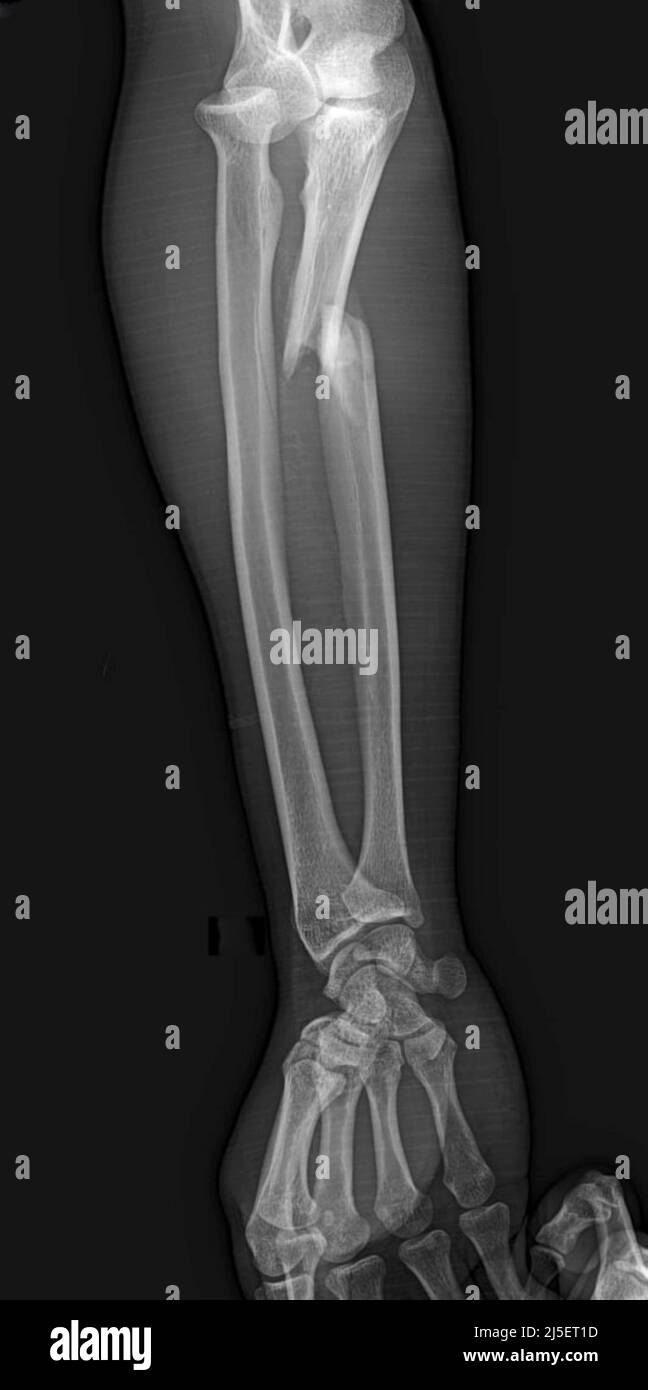

Monteggia Fracture X Ray . A monteggia fracture is defined as a proximal 1/3 ulna fracture with an associated radial head dislocation. The monteggia fracture is a fracture of the proximal ulna associated with dislocation of the radial head. Ap, lateral of elbow, forearm, wrist. Fractures involving coronoid, olecranon, and radial head. Diagnosis is made with forearm and elbow radiographs to check for. Monteggia involves fracture of the ulna with proximal radial dislocation. Proximal 1/3 ulna fracture + radial head dislocation (due to ulna. Galeazzi involves fracture of the radius with distal radioulnar. An examination starts with the visual inspection of the skin, soft tissue, visible bony deformity, skin lacerations, muscle contusion and.

Monteggia fracture, Xray Stock Photo Alamy Monteggia Fracture X Ray A monteggia fracture is defined as a proximal 1/3 ulna fracture with an associated radial head dislocation. Galeazzi involves fracture of the radius with distal radioulnar. Proximal 1/3 ulna fracture + radial head dislocation (due to ulna. Fractures involving coronoid, olecranon, and radial head. The monteggia fracture is a fracture of the proximal ulna associated with dislocation of the radial. Monteggia Fracture X Ray.

Monteggia fracture, Xray Stock Photo Alamy Monteggia Fracture X Ray Ap, lateral of elbow, forearm, wrist. Monteggia involves fracture of the ulna with proximal radial dislocation. An examination starts with the visual inspection of the skin, soft tissue, visible bony deformity, skin lacerations, muscle contusion and. A monteggia fracture is defined as a proximal 1/3 ulna fracture with an associated radial head dislocation. Galeazzi involves fracture of the radius with. Monteggia Fracture X Ray.

Monteggia fracture, Xray Stock Photo Alamy Monteggia Fracture X Ray Ap, lateral of elbow, forearm, wrist. Proximal 1/3 ulna fracture + radial head dislocation (due to ulna. Fractures involving coronoid, olecranon, and radial head. The monteggia fracture is a fracture of the proximal ulna associated with dislocation of the radial head. Diagnosis is made with forearm and elbow radiographs to check for. Galeazzi involves fracture of the radius with distal. Monteggia Fracture X Ray.